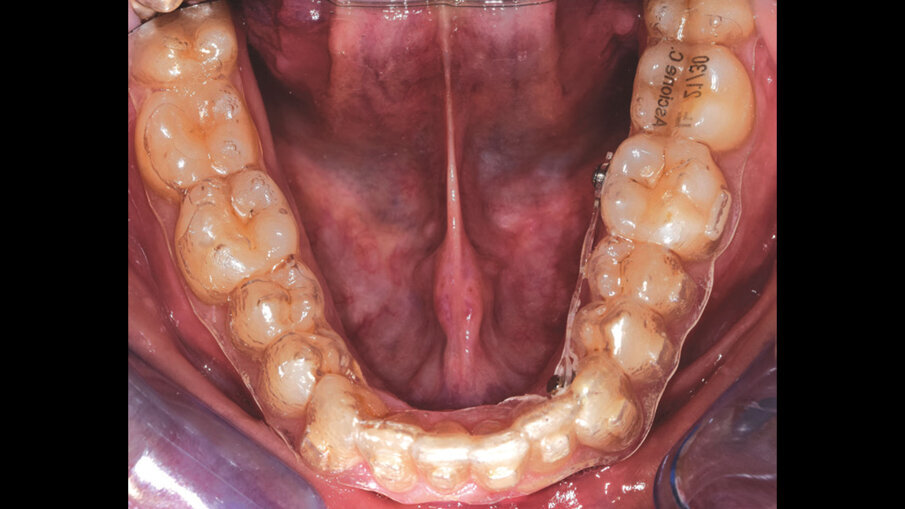

Questo successo ha spinto i produttori a migliorare le caratteristiche dei propri allineatori (materiali, spessore, termoformatura) e introdurre l’utilizzo di dispositivi ausiliari (Figg. 1a-2c) (espansori, bite-ramp, tagli di precisione, elastici), allo scopo di aumentare la predicibilità degli spostamenti dentali ottenibili e la tipologia delle malocclusioni da trattare1-5. Nonostante l’enorme mobilitazione di risorse finanziarie in tutto il mondo, finalizzate alla produzione di nuove linee di prodotti, sono pochi gli studi clinici e le prove di alta qualità sulla reale efficacia di tale trattamento, per stabilire l’affidabilità concreta degli allineatori dentali nella terapia ortodontica; sappiamo sicuramente che la durata di trattamento e il tempo alla poltrona ridotti sembrano essere vantaggi sostanziali degli allineatori rispetto ai sistemi convenzionali, oltre ad assicurare una migliore estetica, un grande comfort, un più facile mantenimento dell’igiene orale e una migliore salute parodontale. Tuttavia, sulla base dell’attuale evidenza scientifica disponibile, la terapia con allineatori dentali è efficace soprattutto nella gestione di malocclusioni lievi e mostra risultati accettabili per il trattamento di malocclusioni moderate6.

Figg. 1a, 1b_Utilizzo di dispositivi ausiliari (REP su miniviti nella foto a sinistra e bottoni linguali con trazione elastica nella foto di destra) per aumentare la predicibilità dei trattamenti con allineatori dentali ALLEO.

Figg. 1a, 1b_Utilizzo di dispositivi ausiliari (REP su miniviti nella foto a sinistra e bottoni linguali con trazione elastica nella foto di destra) per aumentare la predicibilità dei trattamenti con allineatori dentali ALLEO.

Figg. 2a-2c_Utilizzo del dispositivo ALLEO+ come ausiliare per espandere e ottenere spazio in arcata superiore, al fine di utilizzare, successivamente, un numero di allineatori ridotto e una minore quantità di stripping.

Figg. 2a-2c_Utilizzo del dispositivo ALLEO+ come ausiliare per espandere e ottenere spazio in arcata superiore, al fine di utilizzare, successivamente, un numero di allineatori ridotto e una minore quantità di stripping.

Figg. 2a-2c_Utilizzo del dispositivo ALLEO+ come ausiliare per espandere e ottenere spazio in arcata superiore, al fine di utilizzare, successivamente, un numero di allineatori ridotto e una minore quantità di stripping.